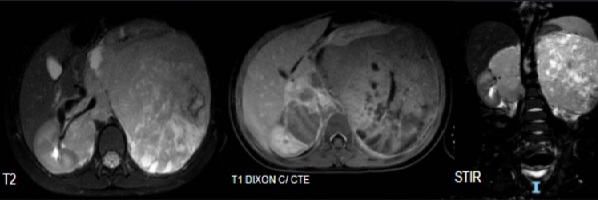

5. RMN Abdomen con contraste:

RMN: Masa retroperitoneal hipointensa en T1, realce heterogéneo con el contraste.

Hiperintensa en T2. Restringe en su mayor proporción y áreas que no restringen en relación

con áreas de necrosis.